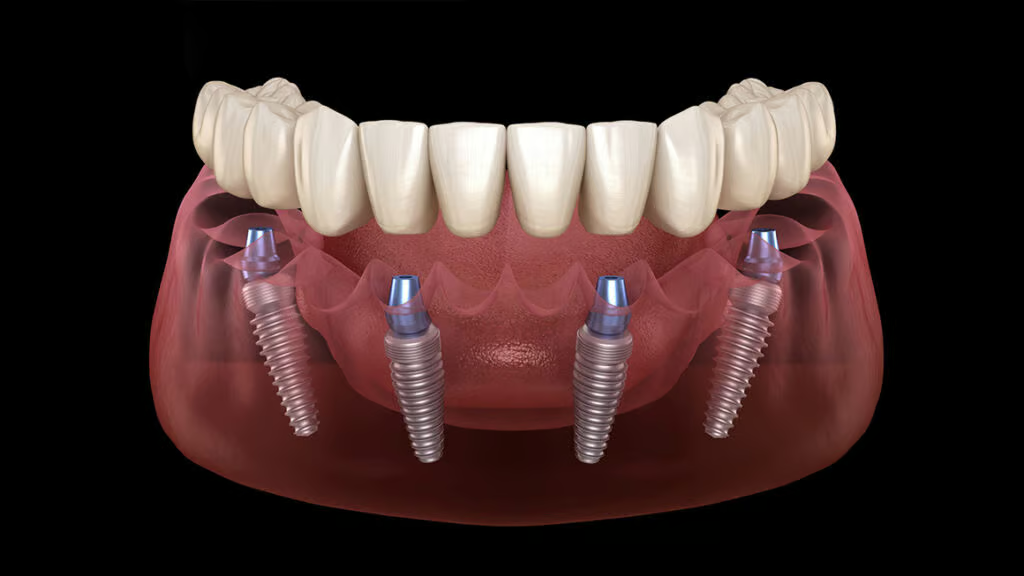

Dental Implants

Restore your smile with modern Swiss, German and American implants. Lifetime warranty included.

Dental Implants

3D tomography, digital smile design, Swiss, German and American implants, zirconia crowns